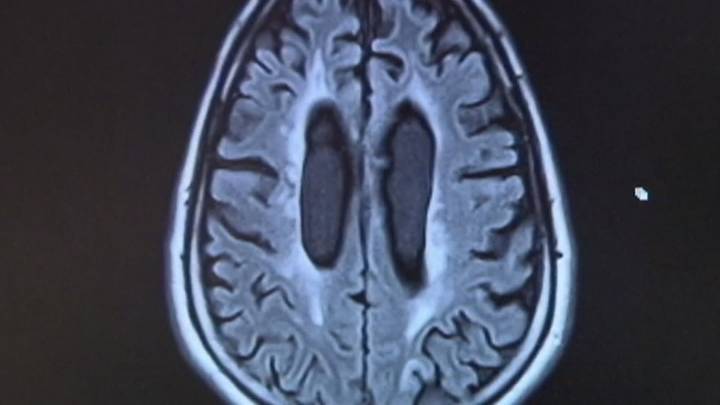

Proposition 14, if approved by voters, would allocate $3 billion from the state’s general revenue to establish the Dementia Prevention and Research Institute of Texas. The funding would support the institute for the next decade, with a mission to advance treatment, prevention, and research into dementia-related diseases.

According to the Alzheimer’s Association, Texas currently ranks third in the nation for dementia cases and second in deaths related to the disease. More than 450,000 older Texans are living with Alzheimer’s disease, according to 2020 data. That’s about 12% of the state’s 65-and-older population.